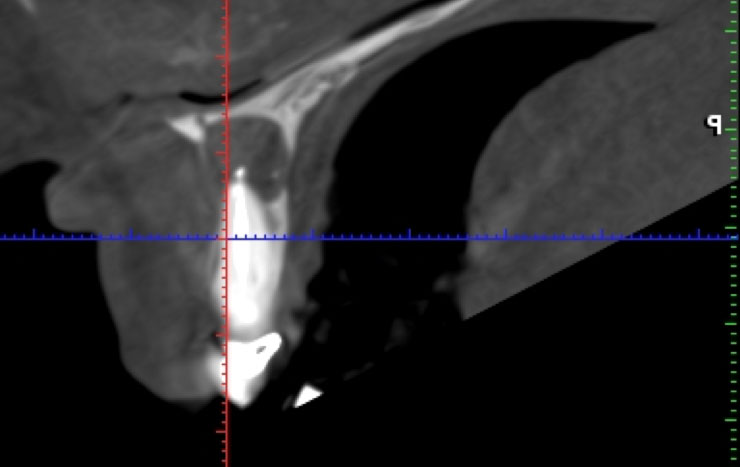

Una radiografía periapical es una técnica radiológica de exploración intraoral con la que podemos observar con detalle el ápice del diente y las estructuras que se encuentran en el área periapical. Nos permite diagnosticar patologías o lesiones periapicales, como el quiste periapical, así como verificar si una endodoncia se ha realizado correctamente y observar el estado de las estructuras periodontales.

Existen dos técnicas diferentes para realizar una radiografía periapical: bisección y paralelismo. Como todas las radiografías intraorales, esta prueba nos permite realizar diagnósticos más completos y precisos e identificar patologías que no se perciben a simple vista.